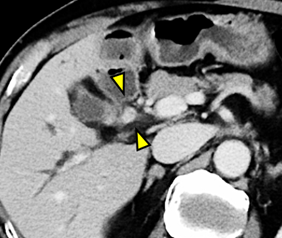

当院の造影CT検査やMRI検査では腫瘍ははっきりとしませんでしたが、たしかに主膵管は拡張していました。

そこで、EUSを行いました。EUSでは、拡張した膵管を途絶するところに、約7mmの小さな低エコー腫瘍(黄色矢頭)を認めました。膵癌の疑いとして、EUS-FNAを行ったころ、腺癌の診断となりました。

EUS所見

左:膵管と途絶する場所に、7mm大の低エコー腫瘤を認めます。

右:この腫瘤に対して、専用の針を用いて穿刺しました。